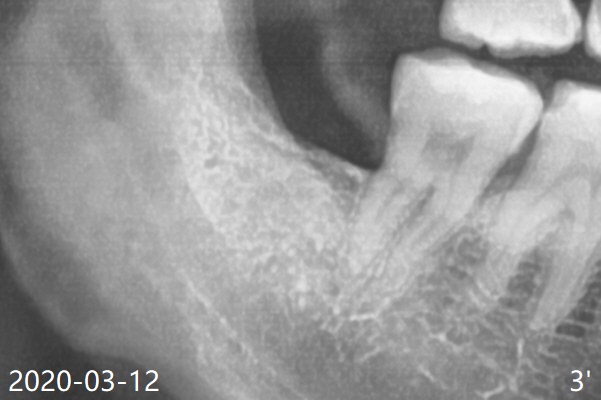

Collagen plug is placed in the extraction socket of #32.

Xin Wei, DDS, PhD, MS 1st edition 03/12/2020, last revision 03/31/2020